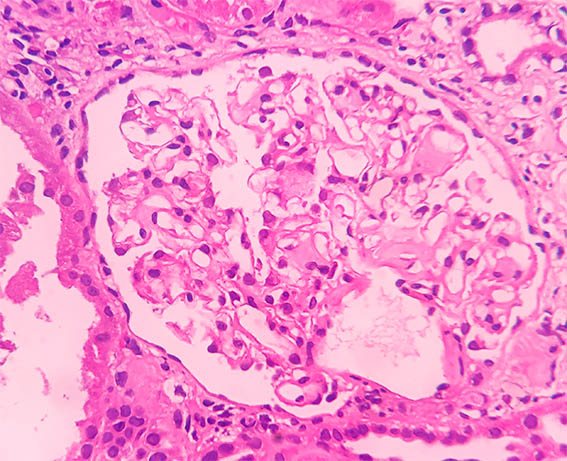

Figure 2. H&E, X200.